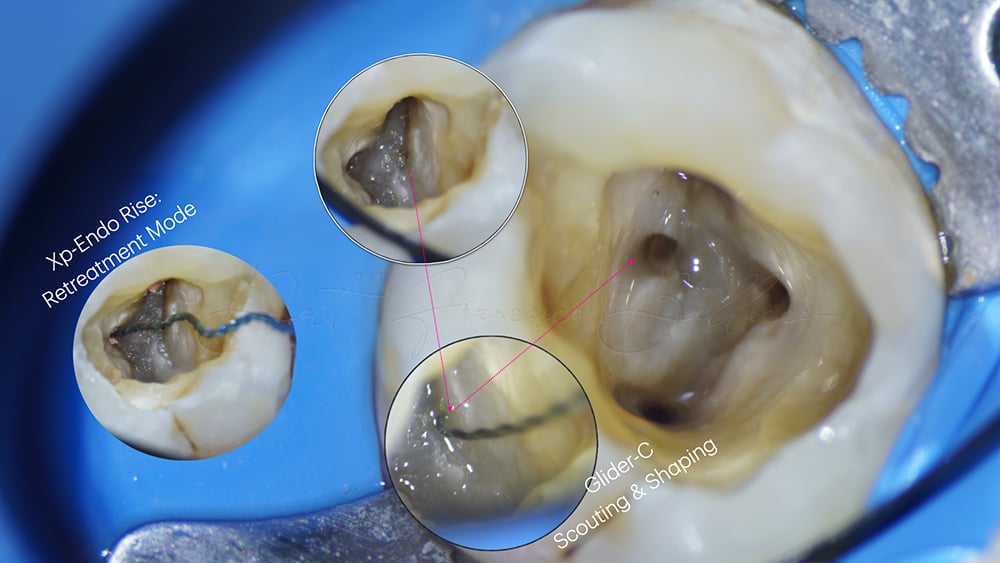

Dopo avere eseguito il disassembling coronale, e avere reperito gli imbocchi, si è provveduto alla rimozione della guttaperca mediante l’ XP-Endo Rise® in modalità da ritrattamento quindi, utilizzando il Rooter 3000 a 2500 rpm come da impostazioni, si è provveduto ad eliminare agevolmente tutto il contenuto.

La parte finale della sagomatura è stata dedicata al canale MB2 non trovato dal precedente trattamento, considerata la forte curvatura della radice, si è optato per un approccio totalmente meccanico eseguendo un o scouting con un Glider-C®, strumento reciprocante austenico con punta 15 e conicità variabile .03-.07. Lì dove lo strumento non proseguiva si utilizzava un R-Motion® 25.06 per creare un allargamento coronale, per poi riprendere l’utilizzo dello strumento da scouting, fino ad arrivare alla WL.

A questo punto la sagomatura veniva ultimata con R-Motion®® 20.04, Race Evo® 25.04 e R-Motion® 30.04.(Fig. 2).